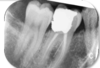

what caused this

Digital (phosphor plate)

- Crescent shaped well defined white mark superimposing the tooth

- Not normal radiographic anatomy

Nail mark

what caused this

Film

- Crescent shaped well defined black mark superimposing the root

Nail mark

what receptor damage is on these images (2 types)

Scraped causing scratches (orange)

Delamination (blue)

- Phosphor layer peel away from edge of image

- Mishandling, wet and drying

- Frayed appearance

Same receptor used twice – bad as obvious damage